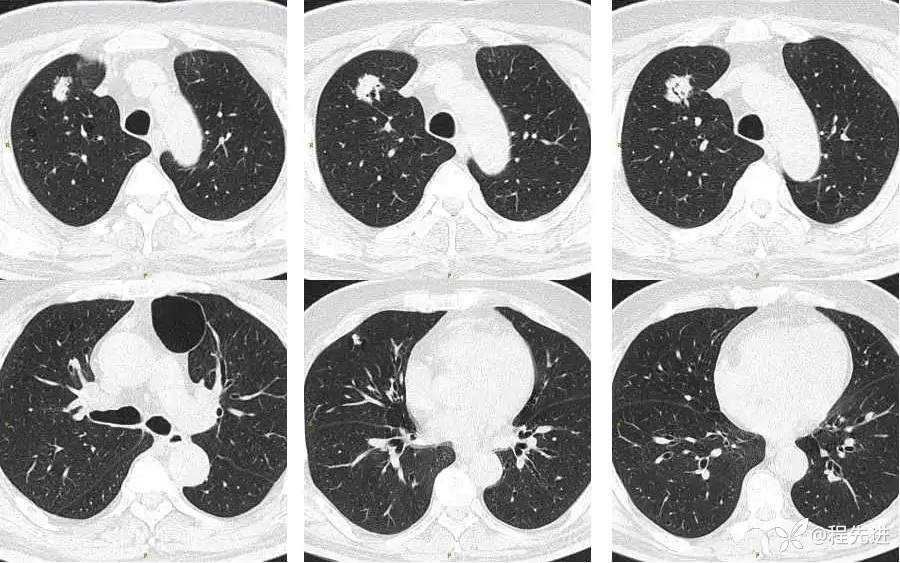

CT平扫:

上排与上面同时间,下排是3月后复查